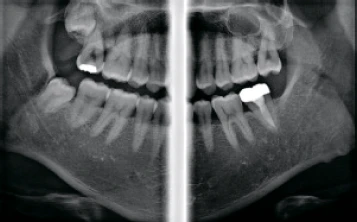

Технология AMF (Адаптивный движущийся фокус) выбирает оптимальный слой изображения для получения чётких панорамных изображений, что позволяет легко определить состояние пародонта пациента и локализацию поражения.